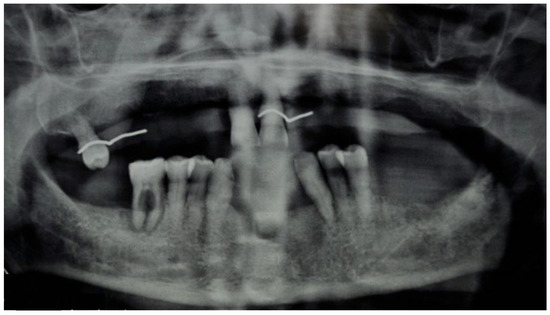

3.1. Clinical Case 1

3.2. Clinical Case 2

3.3. Clinical Case 3

3.4. Clinical Case 4

3.5. Clinical Case 5

3.6. Clinical Case 6